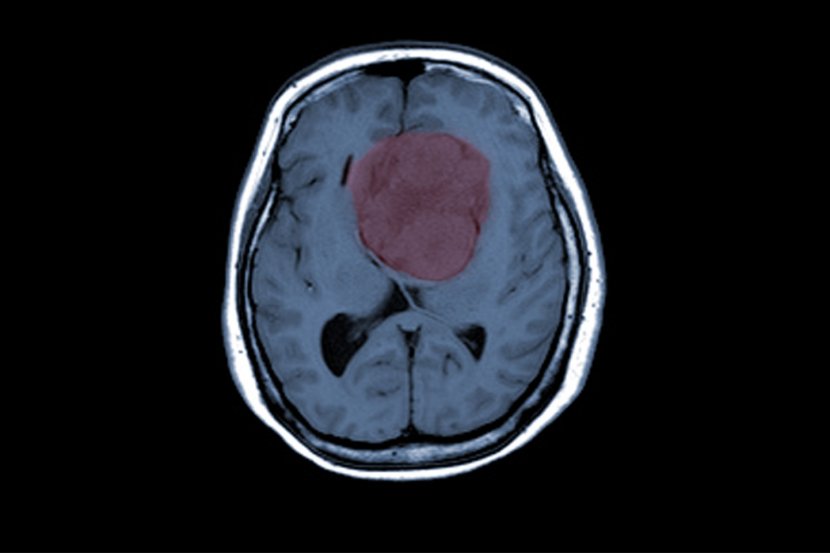

Gestageni su hormonski lekovi, slični prirodnom hormonu progesteronu, koji se dosta koristi za ginekološka stanja kao što su endometrioza i sindrom policističnih jajnika, kao i u hormonskoj terapiji i kontraceptivima u menopauzi. S druge strane, meningiomi su uglavnom nekancerozni tumori u slojevima tkiva (meninge) koji pokrivaju mozak i kičmenu moždinu. Već je poznato da faktori kao što su starija dob, ženski pol i izloženost trima visokim dozama gestagena (nomegestrol, hlormadinon i ciproteron acetat) povećavaju rizik od meningioma. Ali, postoji mnogo drugih gestagena za koje se rizik od meningioma dovodi u vezu sa njihovom upotrebom ali ne postoji pojedinačna procena za svaki od njih.